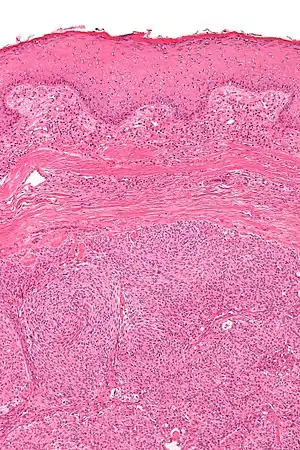

Acrospiroma, solid type

Acrospiroma, clear cell type